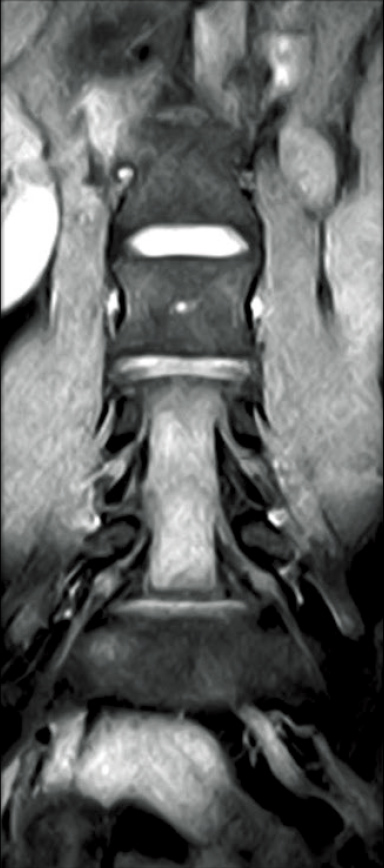

T2WI